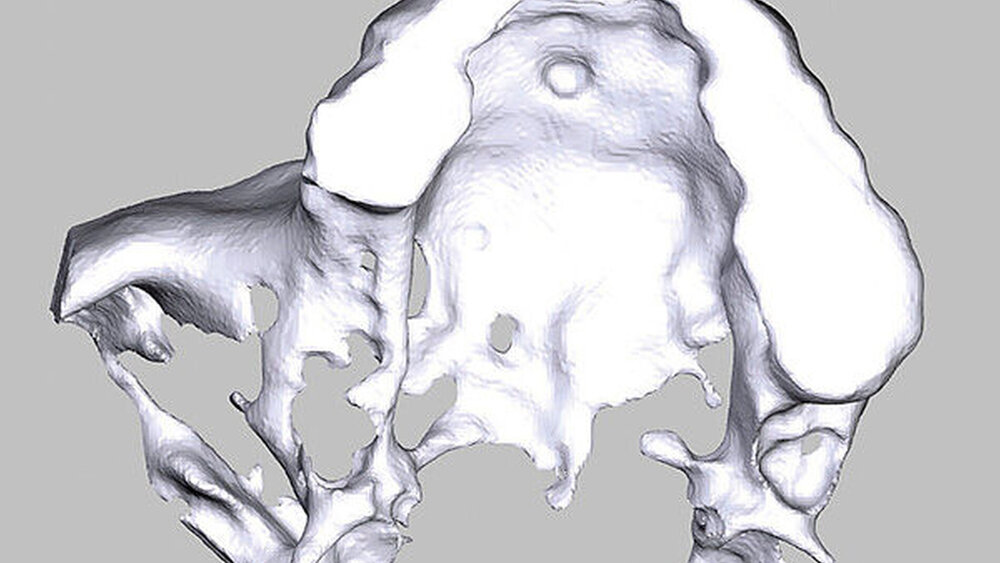

Aufgrund einer ausgeprägten Alveolarkammatrophie im Bereich des rechten Oberkiefers wurde uns eine 62-jährige Patientin zur Augmentation und Implantation überwiesen. Sie hatte ein Implantat regio 16 aufgrund einer Periimplantitis verloren, der Zahn 14 war kurze Zeit vorher extrahiert worden, der Kieferkamm regio 15 war schon lange Jahre zahnlos. Nach wie vor kam für die Patientin nur festsitzender Zahnersatz infrage. Zahn 18 war zwar noch in situ, für eine Brückenversorgung war die Schaltlückenspanne von Zahn 13 auf Zahn 18 aber deutlich zu groß. Nach eingehender klinischer und radiologischer Untersuchung, ausführlicher Besprechung aller Alternativen und einer eingehenden Risikoaufklärung entschied sich die Patientin für die Alveolarkammrekonstruktion mittels CAD/CAM-gefertigtem individualisierten allogenen Knochenblocks. Die DICOM-Daten des angefertigten Oberkiefer-DVTs wurden an die botiss biomaterials GmbH übermittelt. Dort wurde der allogene Spenderblock digital designt, virtuell wurden Implantate aufgestellt und die Planung wurde zur Korrektur zurück an unsere Praxis gesendet. Nach Freigabe durch den Operateur konnte mit der Fertigung des allogenen Blocks begonnen werden.

Nach missglückter Augmentation im rechten Oberkiefer stellte sich ein 42-jähriger Patient in unserer Praxis vor. Für die gewünschten Implantate im rechten Oberkiefer regio 16 und 17 war vertikal deutlich zu wenig Knochen vorhanden. Ein Sinuslift hätte zwar die Höhe des Knochens wieder hergestellt, die prothetische Position der Zahnkronen wäre aber somit in einer Infraokklusion zu liegen gekommen oder die Implanatkronen hätten völlig überdimensioniert werden müssen. Daher entschied sich der Patient für die Rekonstruktion mittels allogenen CAD/CAM-Knochenblocks. Das Prozedere gestaltete sich wie in Fallbeispiel 1. Auch die Einheilzeiten wurden entsprechend eingehalten.

Ein 29-jähriger Patient stellte sich mit einer massiven Alveolarkammatrophie im rechten Unterkiefer in unserer Praxis vor. Diese lag in langen Jahren der Zahnlosigkeit begründet. Eine Beckenkammaugmentation kam für den Patienten nicht in Betracht. Dennoch wünschte er die Versorgung mit festsitzendem Zahnersatz. Nach ausführlicher Beratung entschied sich auch dieser Patient für eine Augmentation mit einem patientenindividualisierten allogenen CAD/CAM-gefertigten Knochenblock. Die DICOM-Daten des Unterkiefer-DVTs wurde an die Firma Zimmer gesendet, und es erfolgten wie im oben beschriebenen Fall eine virtuelle Planung und das virtuelle Design des allogenen Knochenblocks anhand der geplanten Implantatpositionen. Nach der üblichen Kontrolle und Freigabe des Chirurgen erfolgte die eigentliche Fertigung und Übersendung des Knochenblocks in die Praxis. Die Augmentation erfolgte auch in diesem Fall in Vollnarkose unter antibiotischer Abschirmung perioperativ mit Ampicillin. Die Schnittführung im Unterkiefer unterscheidet sich von der Sockelschnittführung im Oberkiefer aufgrund der Anatomie (N. mentalis). Auch bei diesem Patienten wurde eine tief im Vestibulum liegende bogenförmige Inzi‧sion durchgeführt, jedoch ohne die vertikalen Entlastungen. Nach streng subperiostaler Präparation erfolgte die Darstellung des N. mentalis. Die Vorbereitung des Spenderbetts sowie die Wässerung, Einpassung und Befestigung des allogenen Knochenblocks gestalteten sich wie im Fallbeispiel 1. Die Heilzeit des Knochenblocks dauerte ebenfalls sechs Monate. Zwei Implantate (Straumann) wurden nach krestaler Schnittführung in Lokalanästhesie eingebracht und heilten subgingival binnen drei Monaten ein. Aufgrund des massiven Volumenzuwachses war auch ebenfalls eine Vestibulumplastik im Zuge der Implantatfreilegung notwendig. Das Prozedere verlief ebenfalls wie im Fallbeispiel 1. Das freiliegende Gewebe wurde mit einer Kollagenmatrix abgedeckt. Dadurch konnte die Breite der befestigten Gingiva deutlich verbreitert werden.